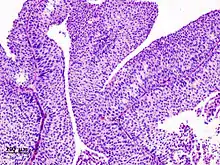

_pT1.JPG.webp)

Non-papillary carcinoma includes carcinoma in situ (CIS), microinvasive carcinoma and frankly invasive carcinoma.[68] Carcinoma in situ (CIS) invariably consists of cytologically high-grade tumour cells.[69]

Transitional cell carcinoma can undergo differentiation (25%) into its variants.[68][70][71] When seen under a microscope, papillary transitional cell carcinoma can present in its typical form or as one of its variations (squamous, glandular differentiation or micropapillary variant). Different variations of non-papillary transitional cell carcinoma are listed below.